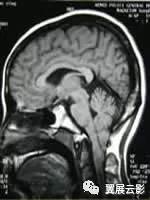

正常脑MRI——

正常脑组织在MRI像上,灰白质界限清楚,在T1WI上白质信号高于灰质,在T2WI上灰质信号高于白质,各脑叶,脑沟,脑裂,脑池及脑室形态自然,无变形及增大或缩小,各中线结构居中。